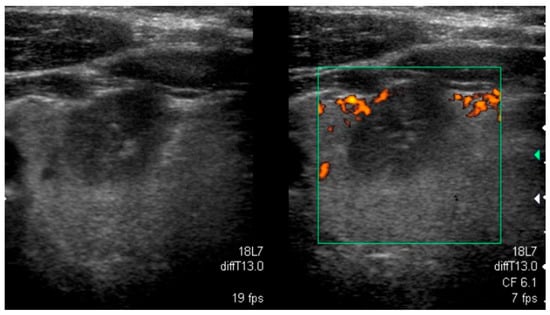

A sonographic pattern typical for PTCs bearing the BRAFV600E mutation is presented in Figure 1.

Figure 1.

Typical sonographic pattern of a BRAFV600E-positive papillary thyroid carcinoma hypoechoic lesion with poorly defined irregular margins and microcalcifications.